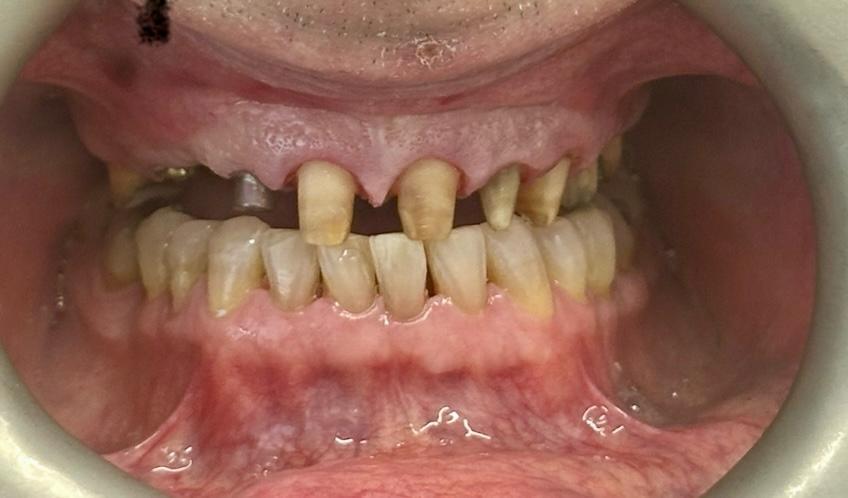

Implants placed using a digitally planned stackable surgical guide following alveolectomy, ensuring ideal positioning and a stable foundation for full-arch restoration.